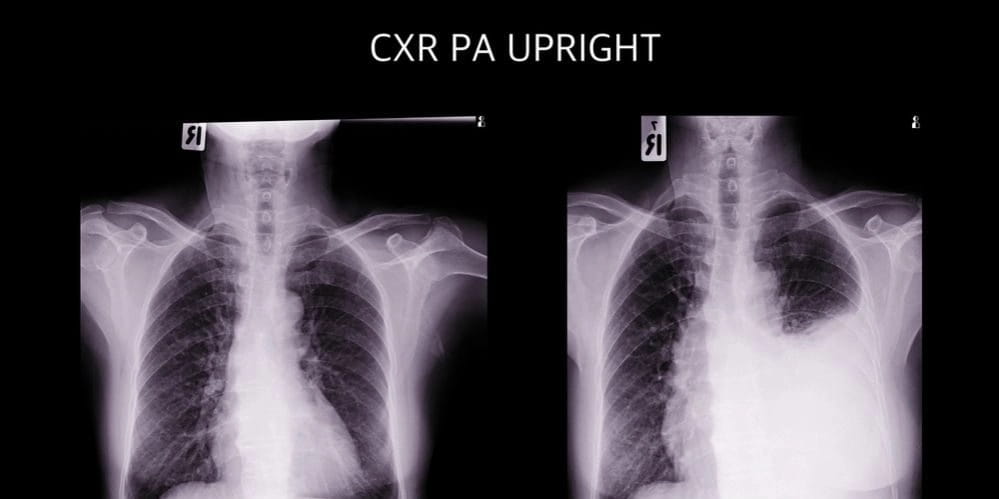

По характеру течения воспаления выделяют сухой и экссудативный плевриты. Дополнительная симптоматика, сопровождающая боль в области сердца при вдохе будет зависеть от особенностей заболевания.

Между плевральными листками скапливается серозный или гнойный выпот. У больных появляется:

При большом скоплении жидкости в полости плевры происходит сдавление легочной ткани, и появляются признаки дыхательной недостаточности:

Появление этих признаков будет свидетельствовать, что легкое не функционирует нормально и необходима срочная помощь.

При появлении дыхательной недостаточности, усиливающей боль в сердце и затрудняющей вдох, проводится удаление скопившейся жидкости через прокол в плевре.

При выявлении плеврита показана госпитализация в пульмонологическое отделение.